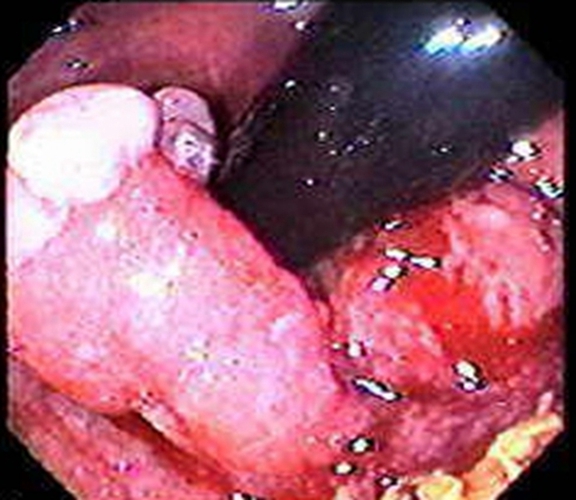

右半結腸癌腺癌